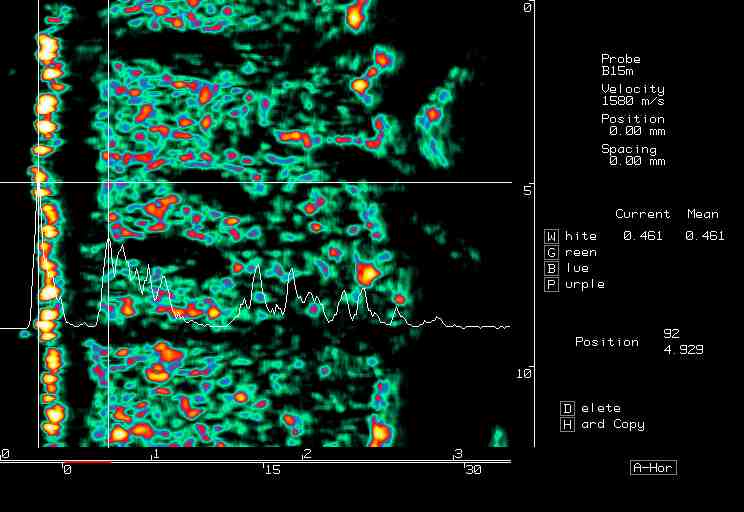

| Dermatofibroma, nevus |  Dermatofibroma |